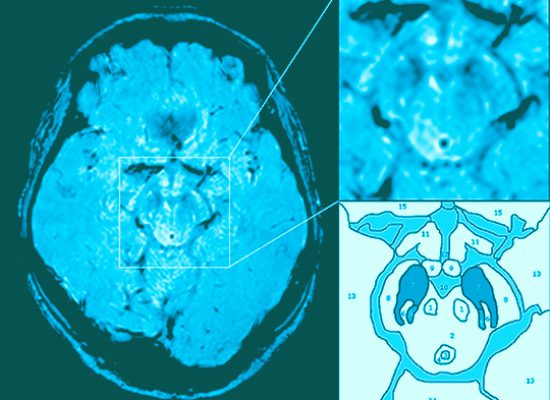

005 Das "swallow tail sign" bei Parkinson